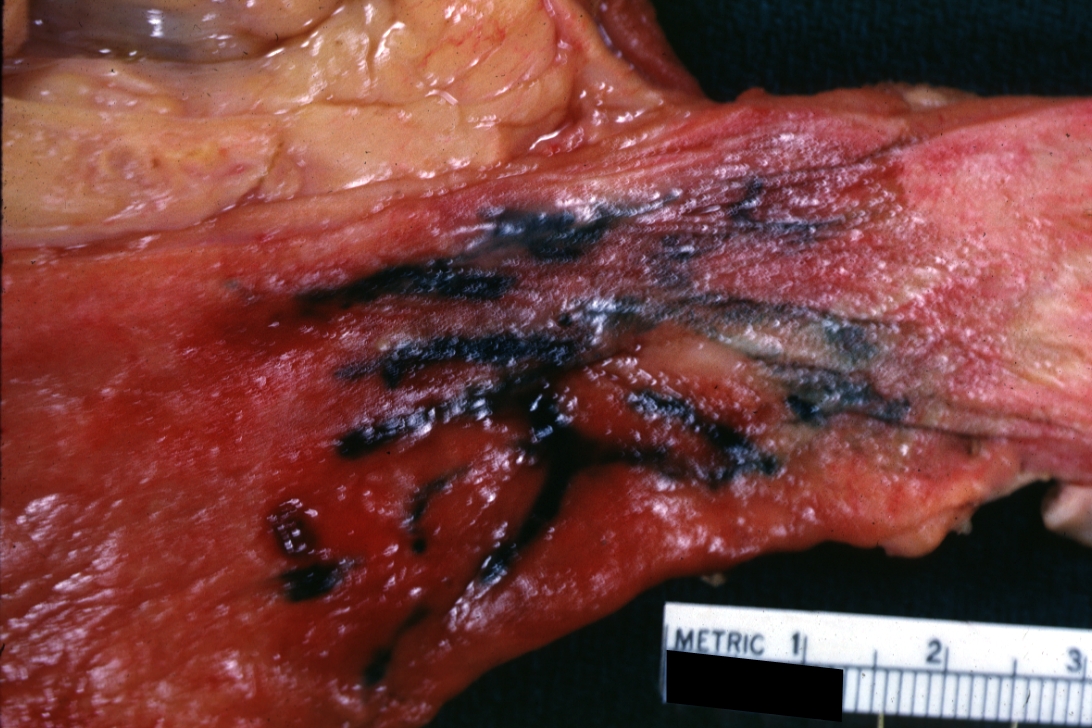

GROSS: GASTROINTESTINAL: Esophagus: Varices: Gross natural color close-up very good demonstration despite highlights